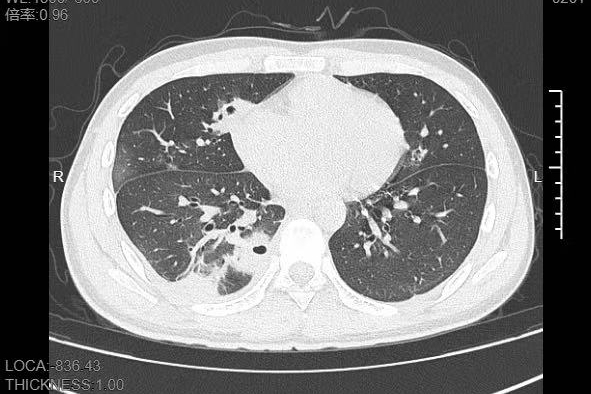

接诊的呼吸与危重症医学科丁群力主任医师一看他的症状,立刻安排了CT检查,结果显示:小林的肺里有十几个空洞,部分肺组织已经坏死,这是典型的血源性肺脓肿